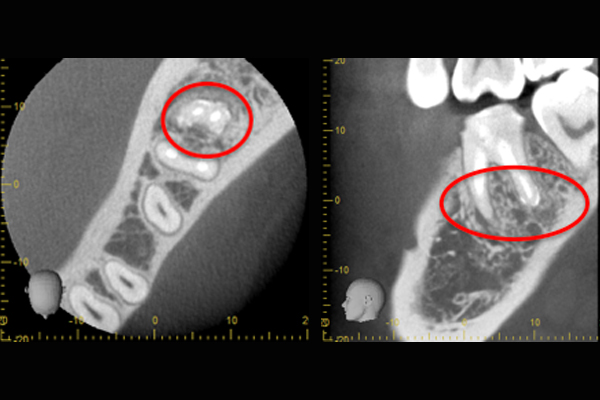

根の横に誤った穴をあけてしまい、気づかずに薬を入れてしまっている。また、器具が破折し、根の先に飛び出ている。

精密根管治療治療終了時歯の側面の穴と根尖はMTAにより緊密に封鎖した。

※本来の根管に薬が入ってることがわかります。